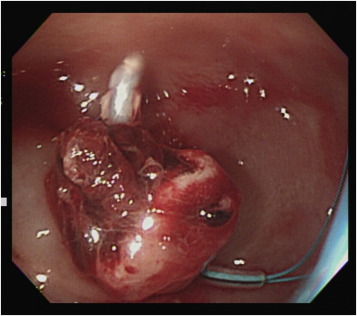

The two endoclips remained in situ , and active bleeding was observed in the narrow gap between the two endoclips. This finding explained the ineffective clipping and the difficult endoscopic approach to the bleeder source. An attempt with a heat probe, coagulation forceps, and further clipping all failed to approach the bleeder. We further attempted to administer an injection of diluted epinephrine in the base of the stalk remnant, and the remnant slowly began rising, giving the appearance of a new polyp. An endoloop was successfully placed beneath the two previously placed endoclips using the tulip-bundle technique, and the bleeding was successfully controlled ( Figure 3 ). The patient was discharged 3 days later without further bleeding.

Endoscopic view after injection and application of an endoloop using the ...

Figure 3.

Endoscopic view after injection and application of an endoloop using the tulip-bundle technique for successful hemostasis.